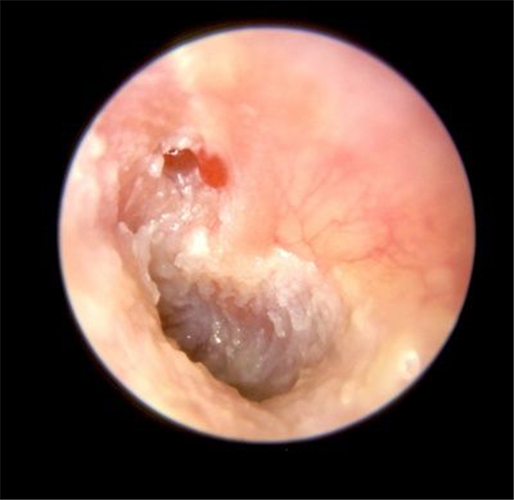

中耳炎鼓膜穿孔